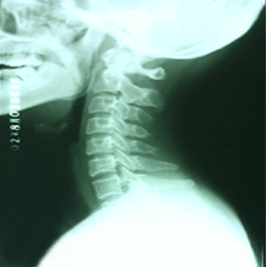

人體端坐或站立時,從側方看人的脖子似乎是直的,但包繞其內的頸椎並不是直的,而是在其中段有一向前凸出的弧度。這一向前的弧形凸起,醫學上稱為頸椎的生理曲度,在X線片上,沿此曲度的走行,在各個頸椎推體後緣連續的一條光滑的弧形曲線,稱之為頸椎生理曲線,正常值為12士5mm。其測量方法是從齒狀突後上緣至第七頸椎椎體後下緣作一直線,上述弧線的最高點至這條直線的最大距離就是頸曲大小的數值。

頸椎曲度的形成是由於頸4~5椎間盤前厚後薄造成的,這是人體生理的需要。它可以增強頸椎的彈性,起到—定的緩衝振盪的作用,防止大腦的損傷。同時,也是頸部脊髓、神經、血管等重要組織正常的解剖生理需要。每當外傷、退變姿勢不良時,不僅可以造成頸椎生理曲度的改變,而且可以因此引起相應的病理改變,從而出現臨床症狀及X線改變等。